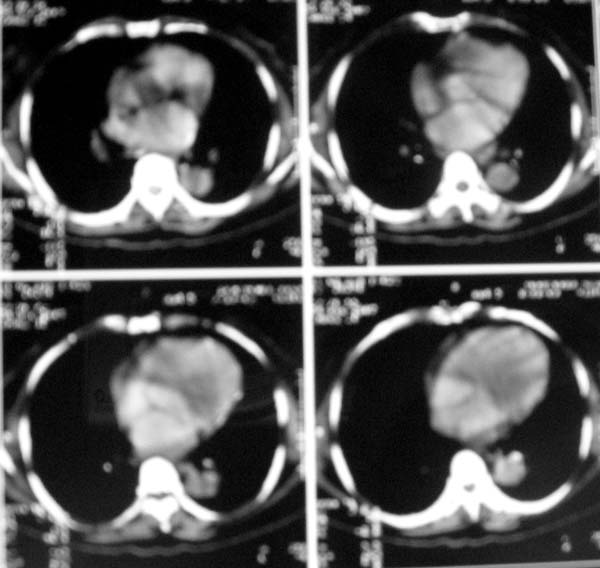

以下是引用zjzjr在2007-8-30 22:22:00的发言:[br]右上肺肺囊肿合并感染.右下肺肺大泡.左肺舌段感染.